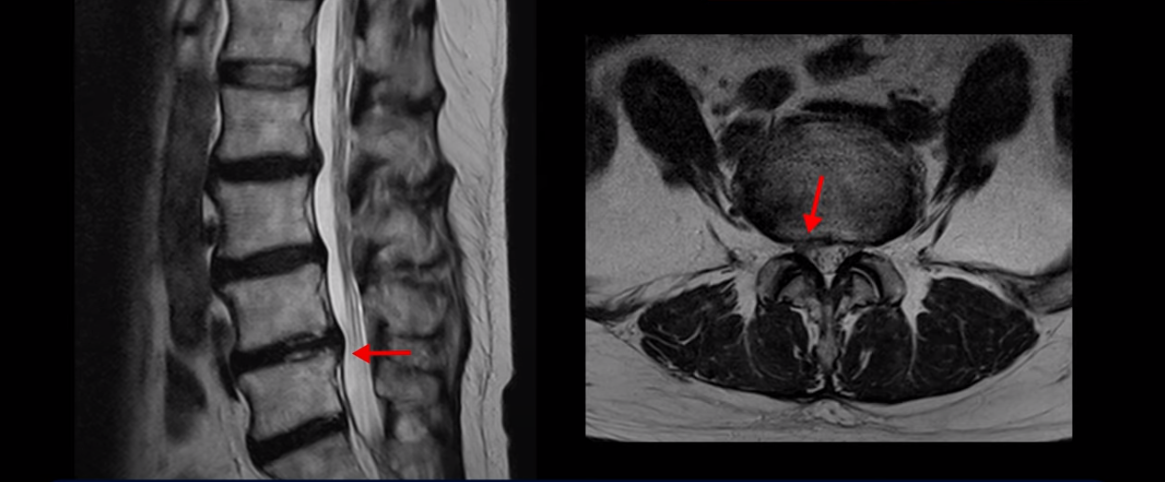

이분 MRI를 보면서 설명 드린 후 어떻게 이렇게 걷지도 못해 휠체어 타시는 환자분이 비수술 치료로 단 몇 주 만에 좋아져서 잘 걷게 될 수 있는지 또 치료는 어떻게 하는지 자세히 설명드리겠습니다.

이분 MRI를 보면 여러 마디가 퇴행이 진행되어 있고

3번 4번과 4번 5번에 중심성 협착이 있는데

4번 5번이 더 심합니다.

또 4번 5번 마디에 오른쪽으로 찢어져서 밀려나온 디스크 탈출이 보입니다.

밀려나온 수핵이 조금 흘러내려 있습니다.